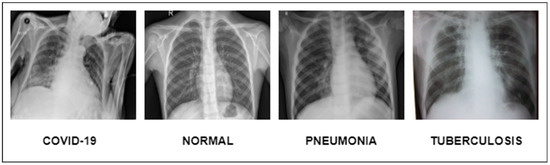

A dataset named Pak-Lungs, which contains 13,313 photos, was used to train and estimate the MixNet-LD model. Images were obtained privately from reputed eye facilities in Pakistan through personal sources. Patients’ and physicians’ permission and willingness to provide data were obtained. It was mutually agreed by the stakeholders that data would be supplied anonymously and that no clinical data would be shared; hence, these conditions kept patient data hidden while making it accessible for study. Both Pak-Lungs and well-known online sources [51] were used as sources for the dataset and the dataset was produced by merging data from numerous Kaggle sources and comprises largely of chest X-ray images associated with various lung illnesses, such as pneumonia, COVID-19, tuberculosis, and normal lung images. The normal and lung disease photos were manually isolated from the dataset acquired by a qualified pulmonologist to construct the training dataset. The pulmonologist detects lung-related traits and establish a standard. The Grad-CAM (gradient-weighted class activation mapping) pre-processing approach marks a major step in improving the interpretability and explainability of deep neural networks, especially in the area of computer vision. Grad-CAM’s capacity to create comprehensible heatmaps that emphasize crucial areas inside an image, together with its ease of use and appropriateness for object localization, makes it an invaluable tool for understanding why a model generates particular predictions. Grad-CAM looks to be preferred above other AI explainability approaches due to its simple implementation, emphasis on localization, ability to provide understandable visuals, and broad use within the deep learning community. While the report does not go into great length about Grad-CAM’s application and rationale, it is clear that this technique was chosen to correspond with the research goals and the requirement for interpretable insights into the model’s decision-making process. Overall, Grad-CAM’s inclusion highlights continuous efforts to improve the transparency and dependability of deep learning models, making them more accessible and trustworthy in many applications, as seen in Figure 3.

Using data from three separate sources, the photos were downsized to a more usual dimension of 700 × 600 pixels in order to simplify and standardize the dataset. Furthermore, during the dataset construction process, experienced pulmonologists contributed to the generation of both lung disease and non-lung disease data for ground truth evaluation. The Grad-Cam technique for image pre-processing was applied to clear the image features and eliminate the interference in the image shown in Figure 2. Using Grad-Cam on the X-ray images enabled us to recognize key regions and ascertain their significance in detecting the existence of pneumonia disease. This technique helps us to identify the distinctive characteristics that greatly influenced CNN’s predictions for the X-ray-based diagnosis of pneumonia pictures.